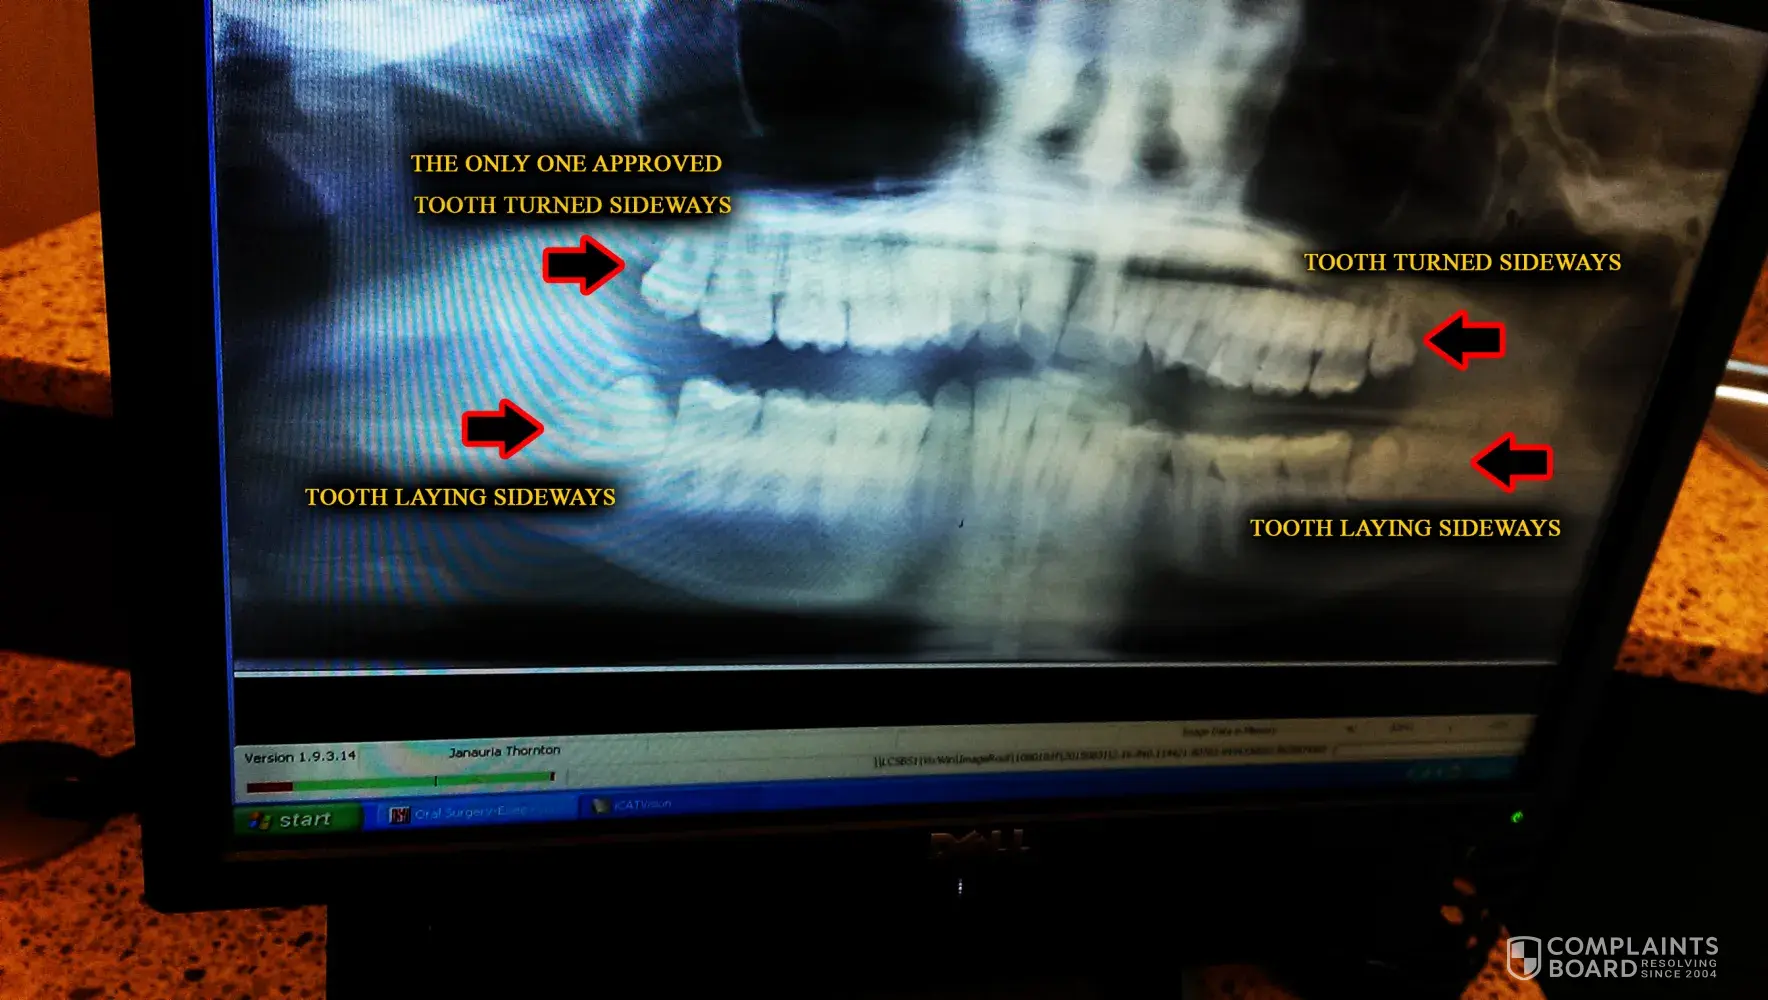

I cannot believe this! Dentaquest approve only one wisdom tooth removal and denied the main ones that I believe are worse... Their reason?... Because the other 3 are incomplete. O. O by the time they're out, her teeth would be pushed together and overlapping even more. What's makes me upset is that not only does this bothers my daughter to not have them all removed, (I have no alternative insurance and very little income) my sister, who uses dentaquest as well, is having all 4 wisdom tooth (That are all incomplete) removed for 2 of her children. She has way more income than me. I don't get this. My daughter's top teeth are turned completely sideways and the bottom wisdom teeth are laying down facing the other teeth with the root embedded into her jaw. I took a picture with my phone of the x-ray results on the dentist computer during the consultation. They even reported that it's medically necessary. Am I missing something, here?!?